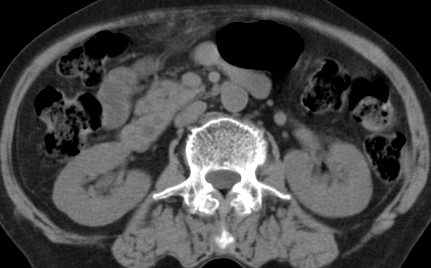

以下是引用齐原在2006-11-8 23:21:00的发言:[br]肝脏体积增大.肝表凸凹不平,肝内胆管扩张,胆总管扩张,胆总管末端突然截断,胰腺勾突增大,形态不规则.胰管扩张.考虑胰头癌.并低位梗阻性胆系扩张,胆囊炎.脾大.建议增强

以下是引用dyqct在2006-11-9 9:14:00的发言:[br]肝大,表面呈波浪状,肝内外胆管扩张,胆总管下端腔内见小结节状等密度影,胰管轻度扩张。胆囊显示不清。[br]考虑:1、胆总管下端占位性病变(等密度结石?壶腹部肿瘤?);[br] 2、肝硬化?[br] 3、建议增强扫描进一步检查。